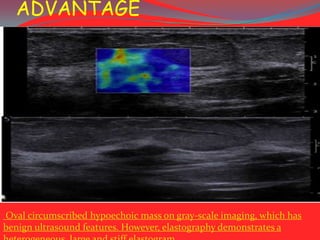

ADVANTAGE

Oval circumscribed hypoechoic mass on gray-scale imaging, which has

benign ultrasound features. However, elastography demonstrates a

ADVANTAGE Oval circumscribed hypoechoicmass on gray-scale imaging, which has benign ultrasound features. However, elastography demonstrates a